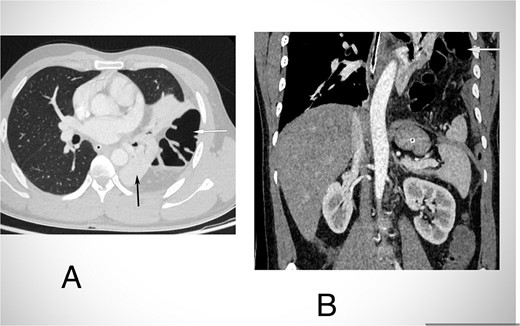

Routine examinations, including total blood counts, differential blood counts, renal function tests, and liver function tests, were within normal limits. The chest X-ray PA view showed the herniation of bowel loops into the left hemithorax with the collapse of the lower zone of the lung with no evidence of previous fracture (Fig. 1). Computed tomography (CT) showed a defect of size around 4 cm with evidence of protrusion of intra-abdominal content in the left hemidiaphragm with basal atelectasis of the left lung and mild dilatation of the jejunal bowel loops with a few air-fluid levels without a transition point (Fig. 2). The patient underwent laparoscopic left diaphragmatic hernia repair with mesh hernioplasty after 6 h of admission. The intraoperative findings revealed a defect of size 4 cm × 2 cm at the posterolateral aspect of the left hemidiaphragm with protrusion of the transverse colon, omentum, and part of the spleen with adhesions (Fig. 3). The content of the hernia was reduced, and primary repair of the defect was done (Fig. 4), and the defect was closed with a 10 × 15 cm intraperitoneal onlay composite mesh (Fig. 5). A postoperative X-ray showed no evidence of herniation of the bowel loops above the left hemidiaphragm (Fig. 6). He was discharged on the fourth postoperative day with oral medications. Follow-up in the outpatient department on the 14th postoperative day showed that he was doing well.

CECT abdomen and lower chest in axial section in lung window (A) and coronal section (B) shows herniation of transverse colon and its mesocolon (white arrow) through a defect in left hemidiaphragm into the hemithorax. There is passive atelectasis of the lower lobe of the left lung (black arrow in A).